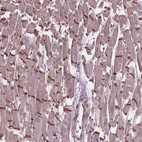

Immunohistochemical staining of human heart muscle shows strong positivity of intercalated discs.